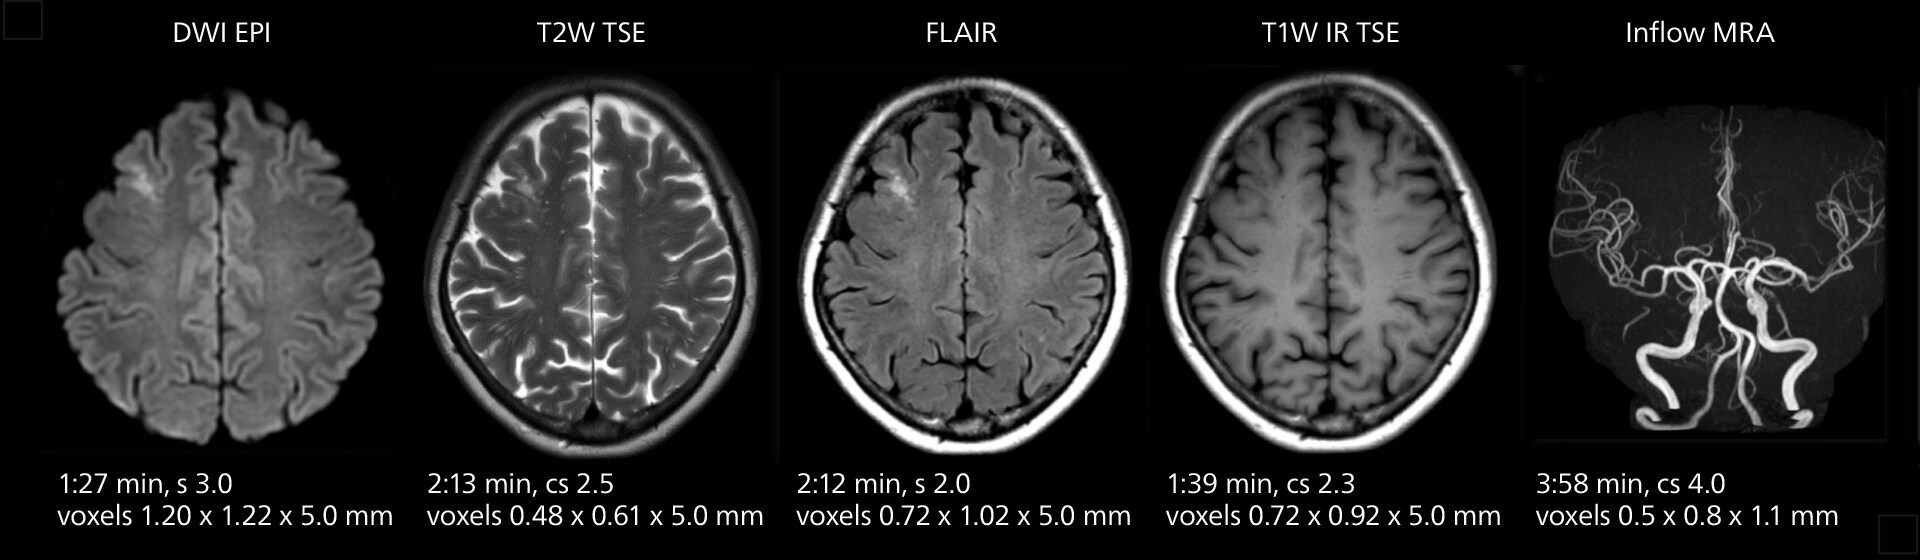

These images of an old cerebral infarction demonstrate the speed and image quality after upgrading to Elition X.